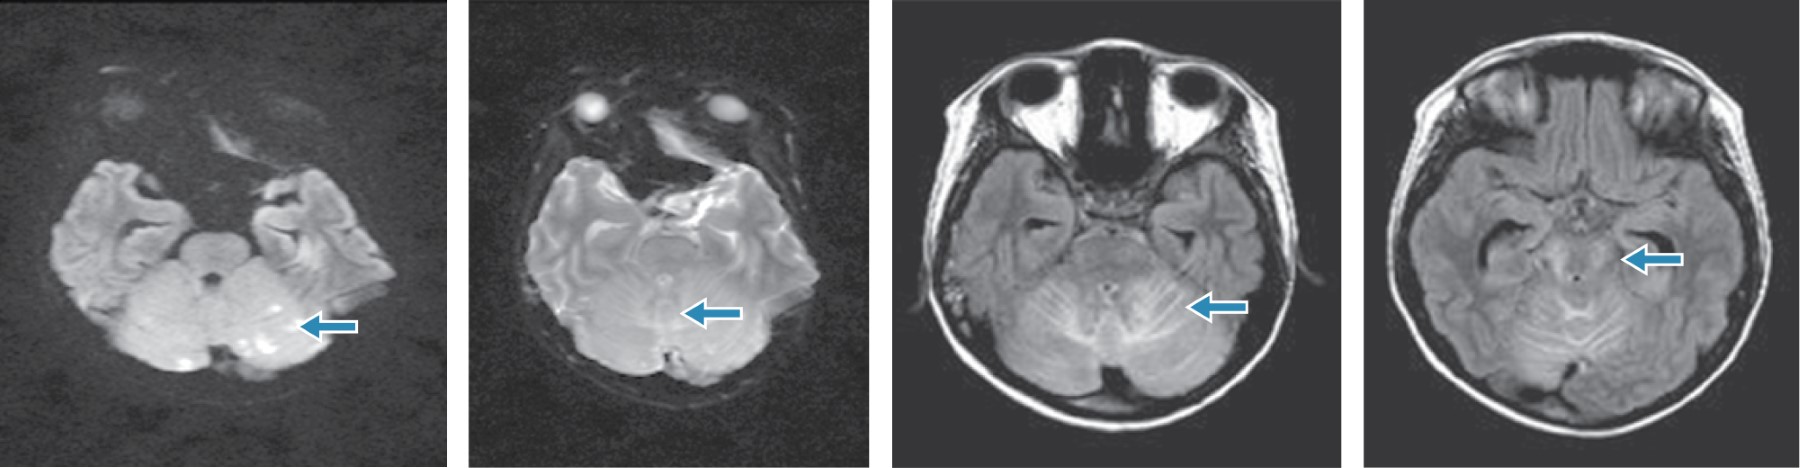

Dentro de los estudios de laboratorio en su abordaje diagnóstico se encontraron leucocitos de 7.9 × 109/L, neutrófilos absolutos 7.1 × 109/L, linfocitos absolutos 0.4 × 109/L, monocitos absolutos 0.5 × 109/L, glucosa 97 mg/dL, creatinina 0.3 mg/dL, sodio sérico 130 mmol/L, potasio 3.7 mmol/L, cloro 88 mmol/L, proteína C reactiva 4.6 mg/dL, procalcitonina 3.2 ng/dL, enzimas hepáticas normales, urocultivo y hemocultivos sin desarrollo. Reporte del líquido cefalorraquídeo: microproteínas 38 mg/dL, lactato deshidrogenasa 12 UI/L, cloro 116 mmol/L, aspecto agua de roca, sin celularidad, panel de encefalitis FilmArray® PCR múltiple negativo, anticuerpos contra M. pneumoniae IgG negativo e IgM positivo, tinta china, tinción Gram, tinción bacterias ácido-alcohol resistentes (BAAR) y cultivos negativos, estudio histopatológico sin infiltración neoplásica. Resonancia magnética (RMN) simple y contrastada de cráneo, con hiperintensidad difusa en secuencia T2 y FLAIR en hemisferio cerebeloso superior e inferior, bilateral, de predominio central y fóveas, con extensión a pedículos cerebelosos posteriores y mesencefálicos; a la administración de contraste se encontró realce de trayecto del nervio óptico en su porción intracraneal, de predominio derecho. Con lo anterior se integran datos de síndrome de PRES asociado a infección por M. pneumoniae, motivo por el cual se indica tratamiento dirigido con levofloxacino a 10 mg/kg/día. Durante la evolución clínica, el paciente no presentó nuevos eventos convulsivos, las cifras tensionales permanecieron normales, no presentó datos de focalización y no se agregaron otros síntomas. A los 13 días, se realiza una nueva RMN de control, donde se observa disminución de la intensidad a nivel de fosa posterior, en relación a estudio previo, sin evidencia de reforzamientos anormales intra- ni extraaxiales que sugieran implantes y neuroeje sin reforzamientos anormormales; angioresonancia normal.

En el síndrome de PRES, la hipertensión arterial se explica de manera hipotética por una perfusión cerebral deficiente, que conlleva a una lesión endotelial mediada por toxinas sistémicas; los factores de riesgo para este síndrome son insuficiencia renal, síndrome nefrótico, nefritis aguda, síndrome hemolítico urémico, dosis altas de esteroides, enfermedades oncológicas y uso de inmunosupresores.8 Sin embargo, en algunos casos, la afección a nivel del sistema nervioso central, puede simular un efecto de masa, simulando neoplasias a este nivel.9 Otros datos que pueden apoyar el diagnóstico son la hipomagnesemia y la afección tradicional en neuroimagen de los lóbulos parietooccipitales, aunque ocasionalmente se observan otras áreas.10 Es importante recordar que a pesar de que las crisis convulsivas son de los datos clínicos más frecuentes, éstas pueden variar en intensidad y características, pudiendo observarse crisis epilépticas no convulsivas con focalización secundaria o de gran mal. La resolución de los hallazgos por RNM es espontánea, en ocho días aproximadamente, por lo que el tratamiento específico es muy importante para delimitar estas lesiones.7,11 El diagnóstico serológico de afección de sistema nervioso central por M. pneumoniae es controversial; habitualmente, los anticuerpos IgM aparecen durante la primera semana de la infección y preceden por dos semanas a los anticuerpos IgG; la detección de IgM positiva en suero en correlación con la clínica compatible sería suficiente para definir la primoinfección por M. pneumoniae, otros autores consideran que para definir la infección del sistema nervioso central se requiere, además de la clínica, detección de IgM positiva en suero y el aumento significativo de títulos de IgG analizados en muestras pareadas, o bien, por detección de PCR positiva en el líquido cefalorraquídeo (LCR) en forma aislada, aunque es infrecuente su hallazgo; por lo que es importante considerar que esta entidad es un reto diagnóstico.12 En el contexto de este paciente, debido a sus manifestaciones clínicas, se abordó de manera inicial para descartar los diagnósticos más frecuentes. Sin embargo, al tener una enfermedad oncológica subyacente, es importante considerar otras posibilidades diagnósticas de forma integral, con lo que se incrementa el pronóstico a corto plazo en este tipo de pacientes (Figuras 1 y 2).